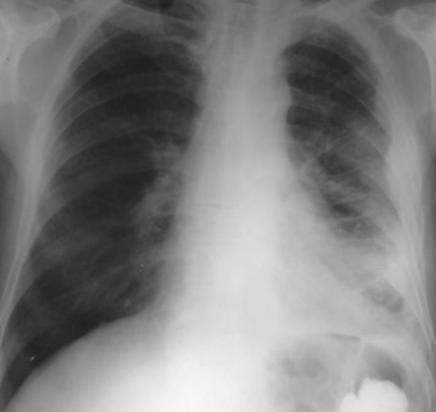

Rx toracică, incidență P-A

DESCRIERE:

pe tot teritoriul pulmonar, bilateral → opacități nodulare multiple de dimensiuni variabile, intensitate medie-mare, omogene, cu contur imprecis delim

confluente

distribuție anarhică

DX: bronhopneumonie

DD:

miliara TBC

MTS pulm hematogene